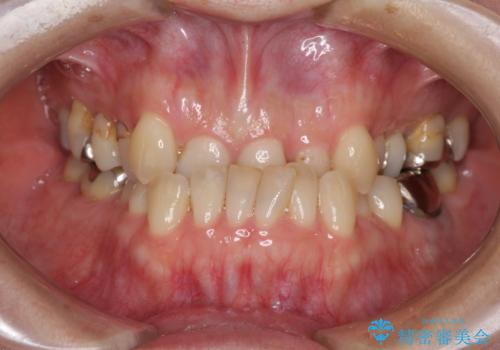

急速拡大装置 前歯の反対咬合をインビザラインで改善

- 前歯の反対咬合を気にして来院された患者様です。

上顎骨の幅が下顎骨よりも小さいので、拡大装置により骨幅を広げて上下関係を改善すると同時にワイヤー矯正で反対咬合の改善を図り、その後インビザラインにて歯並びを整えることとしました。

上顎前歯の矮小歯は矯正治療の途中でオールセラミッククラウンを装着し、左右のバランスを整えることとしました。

急速拡大装置の使用により奥歯の咬み合わせが劇的に変わり、その変化を利用して反対咬合を改善することができました。

治療期間中は奥歯が咬み合わず、食事が取りにくいなどの不都合がありましたが、最終的にはきれいに整えることができました。